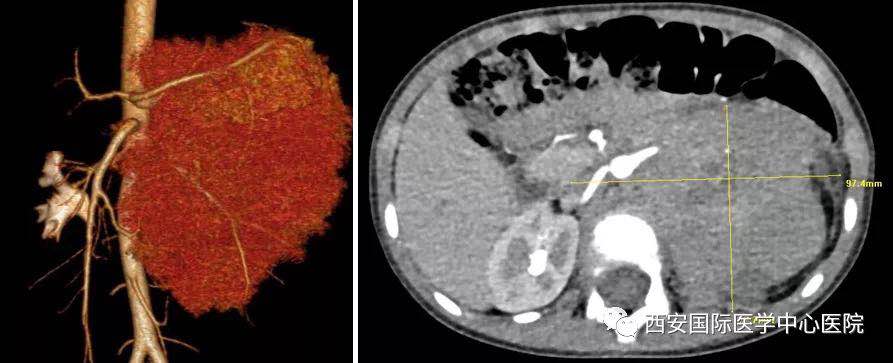

入院后,楊增悅主任仔細(xì)詢(xún)問(wèn)病史、查閱影像學(xué)資料,第一時(shí)間為依依安排骨髓穿刺活檢,最終確診為:腹膜后神經(jīng)母細(xì)胞瘤(Ⅳ期/L2)。CT顯示腫瘤巨大,侵及腹主動(dòng)脈、腹腔干、腸系膜上動(dòng)脈、雙腎動(dòng)脈、腸系膜下動(dòng)脈、下腔靜脈、雙腎靜脈、左腎及腎上腺、胰十二指腸、脾臟、結(jié)腸脾曲;腹膜后多發(fā)淋巴結(jié)轉(zhuǎn)移、骨轉(zhuǎn)移。骨穿病檢示:神經(jīng)母細(xì)胞瘤骨髓轉(zhuǎn)移,腫瘤細(xì)胞占90.5%。經(jīng)過(guò)科室團(tuán)隊(duì)討論后決定,先行新輔助化療后再進(jìn)行手術(shù)治療。